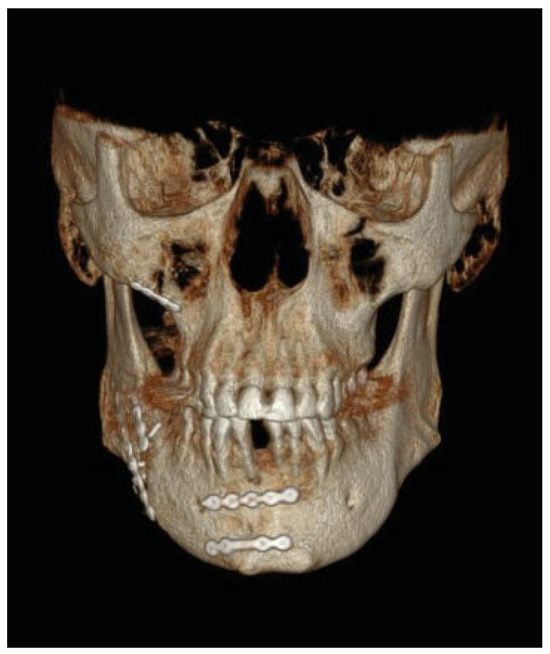

Oral and maxillofacial surgery, ophthalmology, and plastic surgery services were consulted and the patient was brought to the operating room immediately after presentation. Extensive debridement by the plastic surgeons was performed and large defects of facial musculature in the buccal region and lesions of the facial nerve and parotid duct were encountered. The facial artery was damaged and clipped intraoperatively. Much explosive powder residue was removed. After replacement of the oral endotracheal tube with a nasopharyngeal tube, the oral and maxillofacial surgeons approached the fractures of the mandible and maxilla through oral incisions. The fractures were reduced and fixated with titanium plates (Figure 3). Finally, the parotic duct was sutured back into the buccal mucosa and the soft tissue was closed.

Figure 3. Postoperative three-dimensional computed tomography reconstruction image of patient 1 after reconstructive surgery.